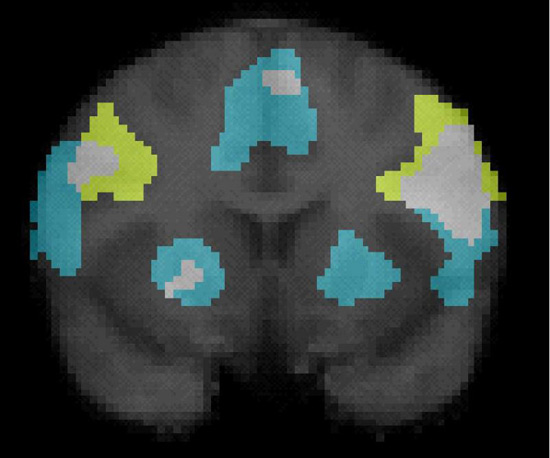

A coronal view of the brain using fMRI, illustrating activity within the mirror neuron system, thought to be essential for emotional response to music.

Musical colors: A coronal view of the brain using fMRI, illustrating activity within the mirror neuron system, thought to be essential for emotional response to music.

Molnar-Szakacs and his colleagues are particularly interested in exploring links between music and two brain networks: the limbic system and the mirror neuron system.

The limbic system is an interconnected series of brain structures ― including the hippocampus and amygdala ― that process emotions such as happiness and fear. Mirror neurons are cells in the premotor cortex and parietal cortex that fire when people watch or imitate other peopleʼs actions and interpret their intentions.

Although mirror neurons are most often associated with seeing and understanding actions, there is evidence that they may also help decipher meaning and emotion in music3.